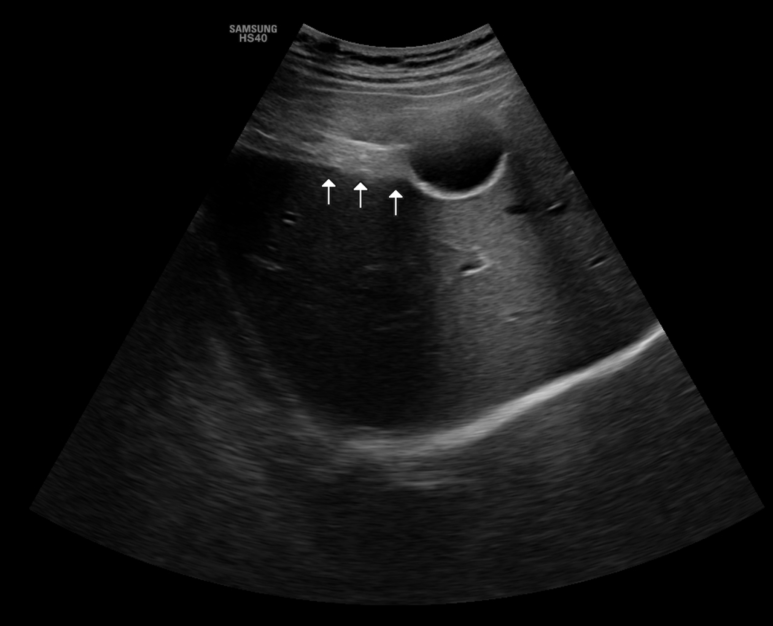

40대 초반 여자, 초진 2~3일전부터 조금씩 불편하다가... 오늘 새벽 (am1) 부터 복통이 심하고.. 위아래다가..콕콕/짜는거 같기도 하고.. 계속 구역질 두들겨 맞은거처럼 아프고 온몸이.. 과거력 24넌말 담낭절제 촉신상 우상복부에 뚜렷한 압통 담낭이 없는데 지속되는 담낭산통의 느낌... 총담관 폐색/폐쇄? 를 고려하여 초음파 시행 총담관 직경; 경계가 뚜렷하지 않아 측정하지 않음 간내 담관, IHBD의 확장은 관찰되지 않음 의심되는 (후방감쇄는 없는 고음영) 돌이 원위부 총담관에, 0.99 cm; 그러나, 십이지장의 공기와 구별하기 위해 반복해서 확인함, 검사 종료전 재확인시에는 주변장기등 위치변화에 의해 재현이 잘 되지 않는 느낌 수직보기에서 수평보기에서... 이 사진에서는 위쪽으로 공기층이 겹치는 듯 수직, vertical view로 보았을 때 조금만 내측으로 프로브를 기울이면 십이지장 공기가 보이는데, 따라서 총